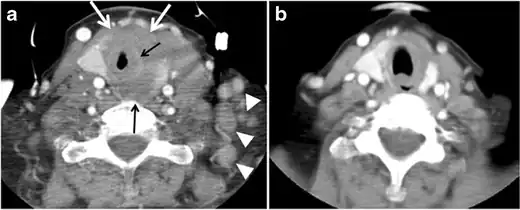

Fig. 11. Thyroid non-Hodgkin's large B-cell lymphoma in a 66-year-old female patient. an Axial enhanced neck CT scan demonstrates left thyroid lobe and isthmus homogeneously hypodense and minimally enhancing mass (white arrows). This lesion invades the prevertebral muscles (black arrows). Note the multiple enlarged level V lymph nodes (white arrowheads). b Post-treatment image shows significant reduction in size and mass effect of the left thyroid infiltrative mass, with almost complete resolution of the left cervical lymphadenopathy.[1] -